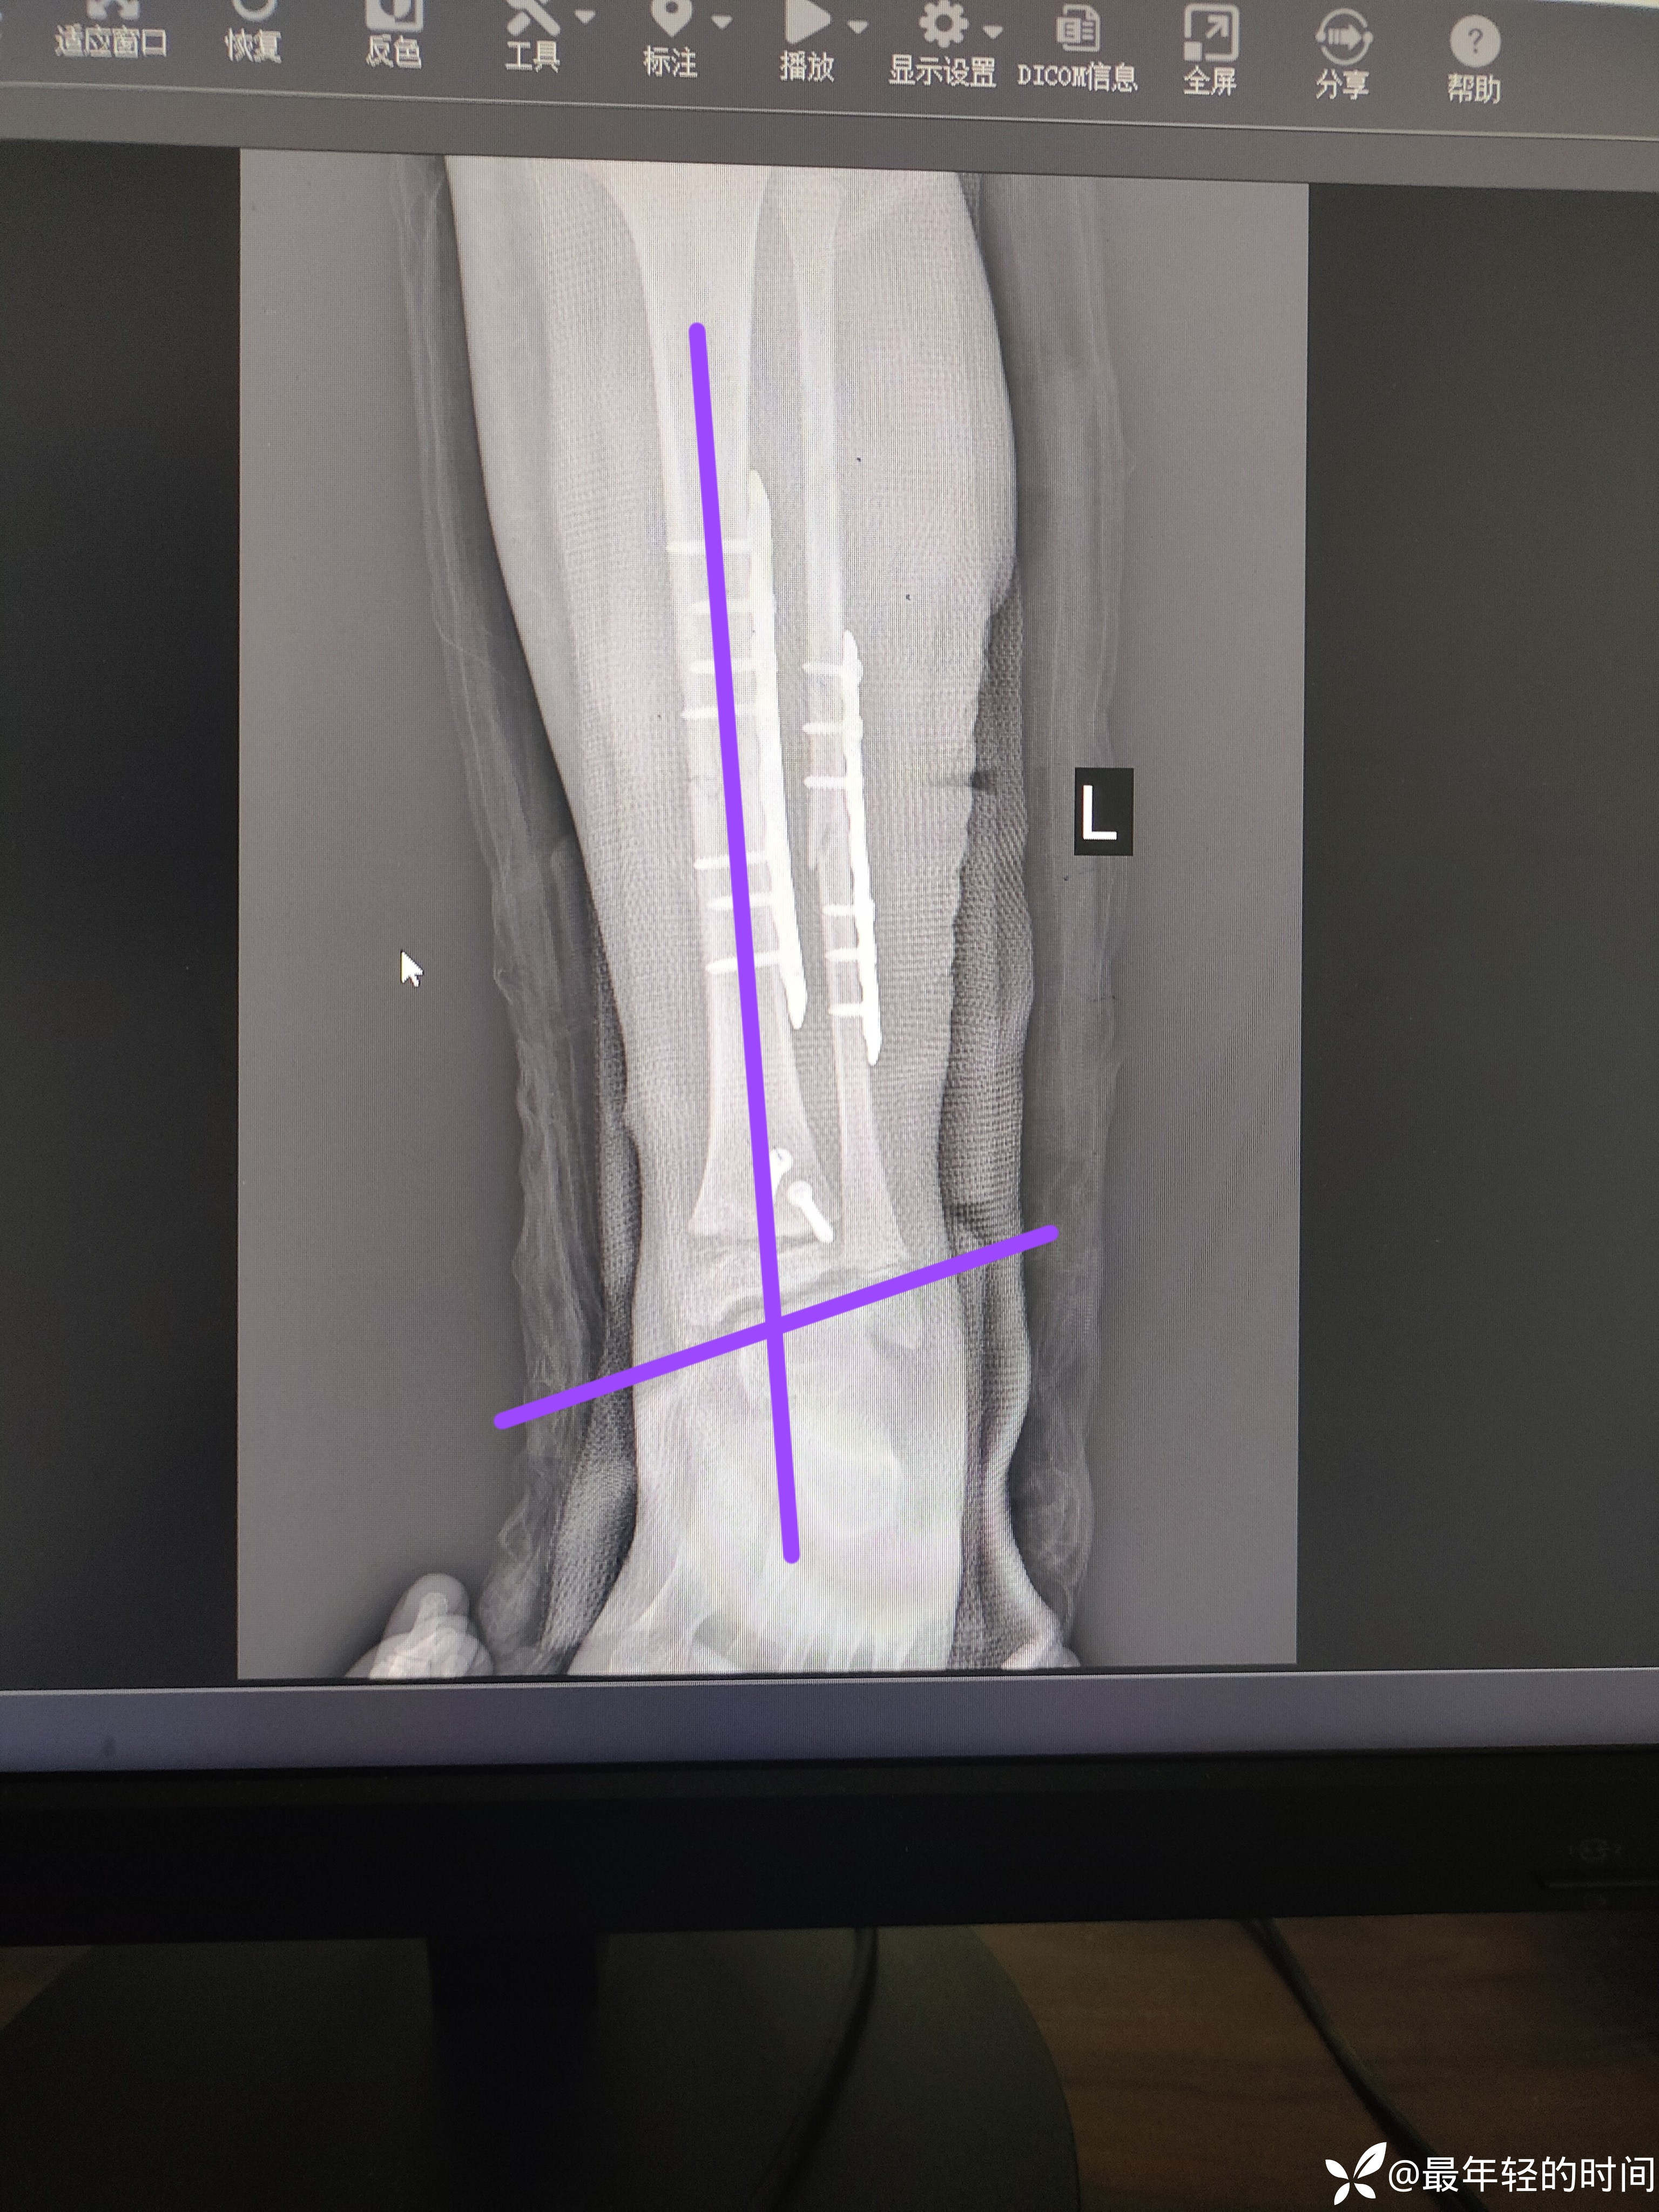

消肿后行切开复位钢板螺钉内固定。术后患儿足踝部及足背部疼痛剧烈,目前术后一周,疼痛症状任未有效缓解。术后片如下:

手术方式我本就不赞同,我更倾向于弹性髓内钉固定胫腓骨骨干,解剖复位骨骺损伤螺钉固定后踝(本例手术是同科室另外一组人做的)。各位老师看看术后片有没有发现问题所在呢?我也简单的分析了一下。虽然科主任听了我提出的问题表示的很不屑,但是我还是坚信自己。这里想请教各位儿骨的老师们,这个手术对该患儿踝关节的功能会有什么样的影响?如果影响比较大,现在最好的处理方式是什么?

懂得人一看就懂,其实后踝和骨骺的复位也不是太理想的。踝穴外翻,踝关节承重不平衡。个人觉得对患者功能影响应该是挺大的。我也不想诋毁同行,只想请教一下各位老师,像这种情况会不会在生长发育的过程中得以纠正?如果不能,现在最好的补救措施是什么?